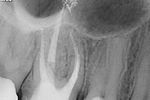

Revisionsbehandlung eines Unterkiefermolaren (37) vor geplanter Überkronung (Dr. Maik Göbbels) Download